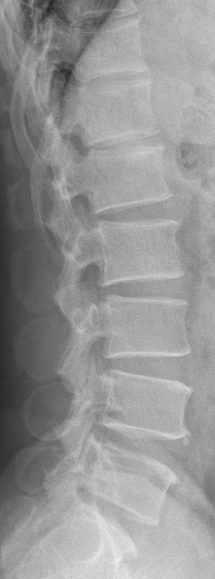

主诉:左下肢麻痛半年,加重伴乏力2周。 病史:患者半年前无明显诱因出现左下肢麻痛,腰部疼痛不明显,久站后有酸胀感。加重伴乏力2周;患者目前无二便失常。患者一般情况尚可。

体查:脊柱无明显畸形侧凸。各棘突及棘旁无明显压痛;左下肢肌力较右侧稍减弱,余四肢肌张力、感觉等无明显异常;双侧膝反射、踝反射无明显异常。病理征未引出。 辅助检查:三大常规、血生化检查未见明显异常,主要脊柱影像学检查如下,请参阅。

诊断:T12-L1椎管内肿物 治疗:患者入院后尽快完善相关检查,请神经外科会诊。经治疗组讨论,拟行“T12-L1椎管内肿物切除+钉棒内固定术”。

讨论:患者椎管内肿物,从影像学表现上看,主要考虑神经鞘瘤,但确诊需依靠手术的病理,同时根据患者的病理情况决定下一步治疗。